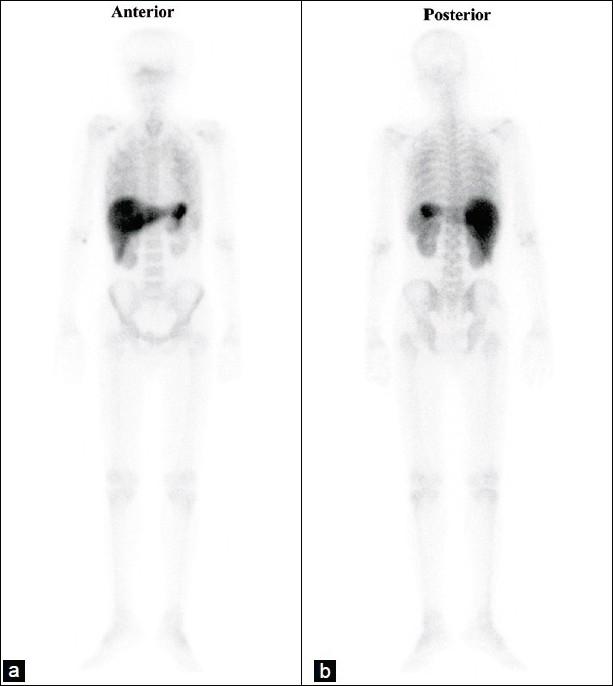

Diffuse hepatic and splenic Tc-99m MDP tracer uptake in case of multiple myeloma.

Tc-99m methylene diphosphonate (MDP) bone scintigraphy has long been used for the evaluation of benign as well as malignant skeletal conditions. However, non-osseous tracer uptake on a bone scan is an unusual finding. There is a need to understand the pathophysiological basis of the non-osseous uptake, which may have a clinical relevance or deteriorating effect on the quality of the bone scan. We describe a case of multiple myeloma, where extraosseous uptake in the form of diffuse hepatic and splenic uptake, with almost normal skeletal tracer distribution, has been seen on the bone scan.